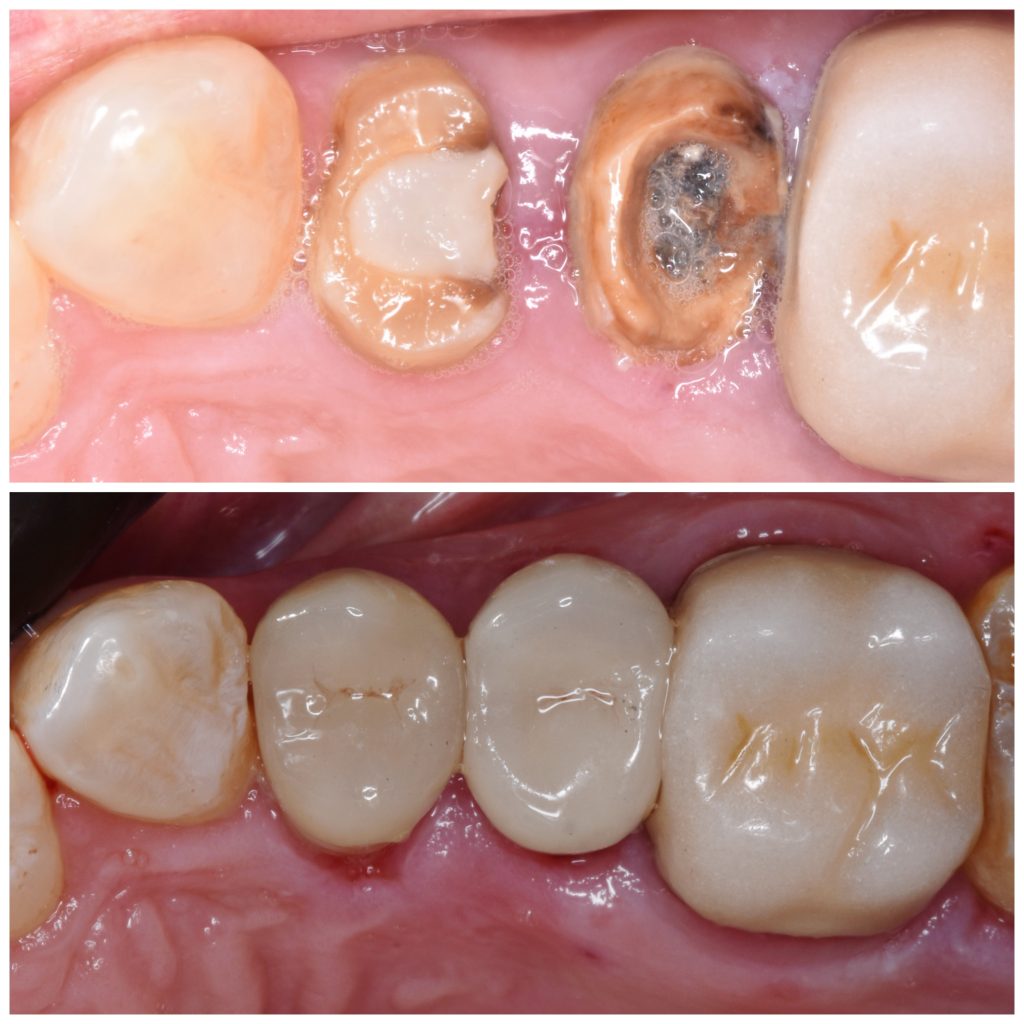

Upper right first and second premolars

Were badly decayed

Rubber dam isolation is mandatory in such cases

Caries removal with aid of caries detector dye

Deep margin elevation using circumferencial Copper bands

Elevation by snow plow technique n

And final design to receive to monolithic lithium disilicate restorations

Cementation by heated composite

Shofu beautifill LS